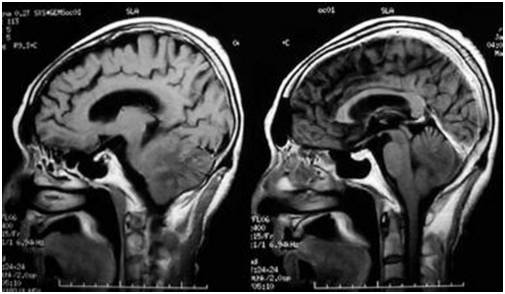

脑转移瘤系指原发于身体其他部位的肿瘤细胞转入颅内,其中以肺癌脑转移最常见。在许多恶性程度高的肿瘤中,发现有20%-40%发生脑转移。目前针对脑转移瘤尚缺乏有效的治疗策略,许多患者发生脑转移瘤后不到12个月,即死亡。因此,急需研究开发出更好的治疗策略。

近几年,关于脑转移瘤的分子以及细胞机制得到了一定的阐释:循环肿瘤细胞首先通过血脑屏障(blood–brain barrier, BBB)进入软细胞组织。许多进入软细胞组织的肿瘤细胞被星形胶质细胞消灭。星形胶质细胞在中枢神经系统中发挥营养、保护作用,大概就是这样的——

在脑转移瘤中,研究发现活化的星形胶质细胞产生血纤维蛋白溶酶原和细胞毒性细胞因子对脑转移癌细胞发挥作用,然而脑转移瘤细胞通过丝氨酸蛋白酶抑制剂抑制因子拮抗活化星形胶质细胞产生的血纤维蛋白溶酶原作用,从而使自身不被清除。但星形胶质细胞和癌细胞之间并不总是拮抗关系:脑转移瘤包含许多活化星形胶质细胞,星形胶质细胞在与癌细胞共培养时,对癌细胞有益处。然而其具体作用和分子机制尚不明确。

作者研究发现在脑转移瘤中,存在较高的Cx43的表达,对比脑转移瘤、原发肿瘤和正常组织,也观察到脑转移瘤中高水平的Cx43,Cx43是间隙连接组成的分子。为了更好的观察癌细胞-星形胶质细胞的联系,作者运用了5个来源于人和小鼠的脑转移瘤模型:乳腺癌(MDA231-BrM2和ErbB2-BrM),肺癌(H2030-BrM3, 393N1和LLC-BrM)。细致观察发现Cx43表达在癌细胞-星形胶质细胞接触处,在星形胶质细胞中表达最高,PCDH7在乳腺癌和肺癌中高表达,同时在脑转移瘤中,PCDH7水平较高,而且在脑转移癌细胞中的含量高于星形胶质细胞、小胶质细胞或内皮细胞。在临床三阴乳腺癌(triple-negative breast cancer, TNBC)中,发现原发肿瘤中Cx43和PCDH7的含量与脑转移有关,而不是骨转移或者肺转移。在非小细胞肺癌(non-small cell lung cancer, NSCLC)也观察到同样的现象。这些证据表明Cx43主要表达与星形胶质细胞,PCDH7主要表达与癌细胞,Cx43和PCDH7与脑转移瘤相关。